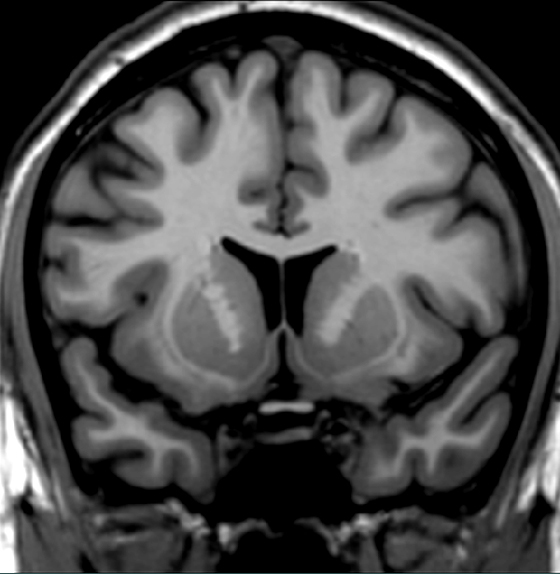

Identify one subcortical region that receives a substantial dopaminergic input from the ventral tegmental area.